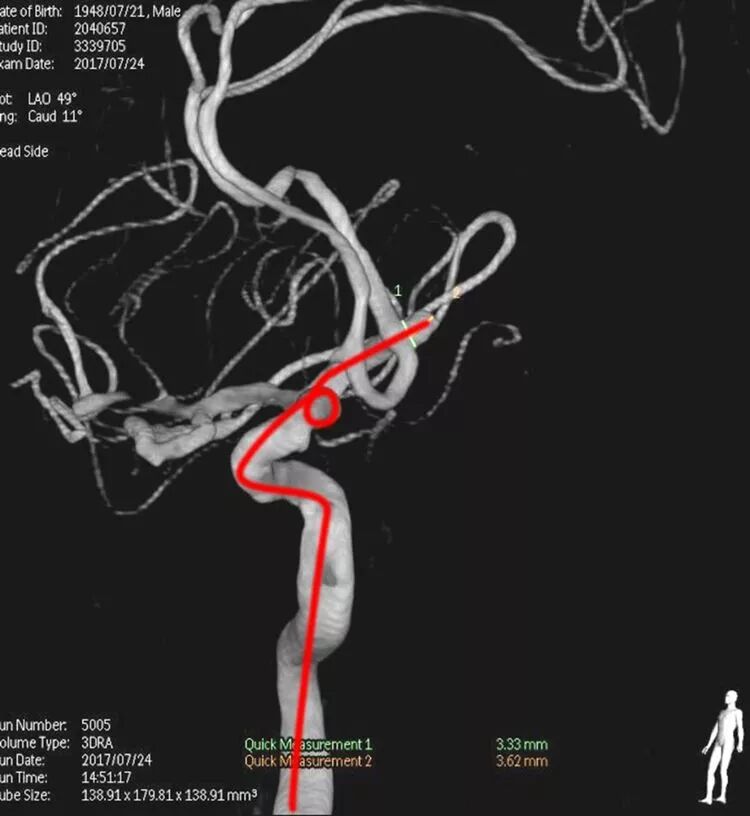

基底动脉顶端宽颈动脉瘤

应用Solitaire支架结合双微管栓塞,一根微导管是45°预塑形的,管头置于瘤体中央(浅管),另一根微导管管头塑成C形,沿瘤底深入到瘤体右侧角(深管)